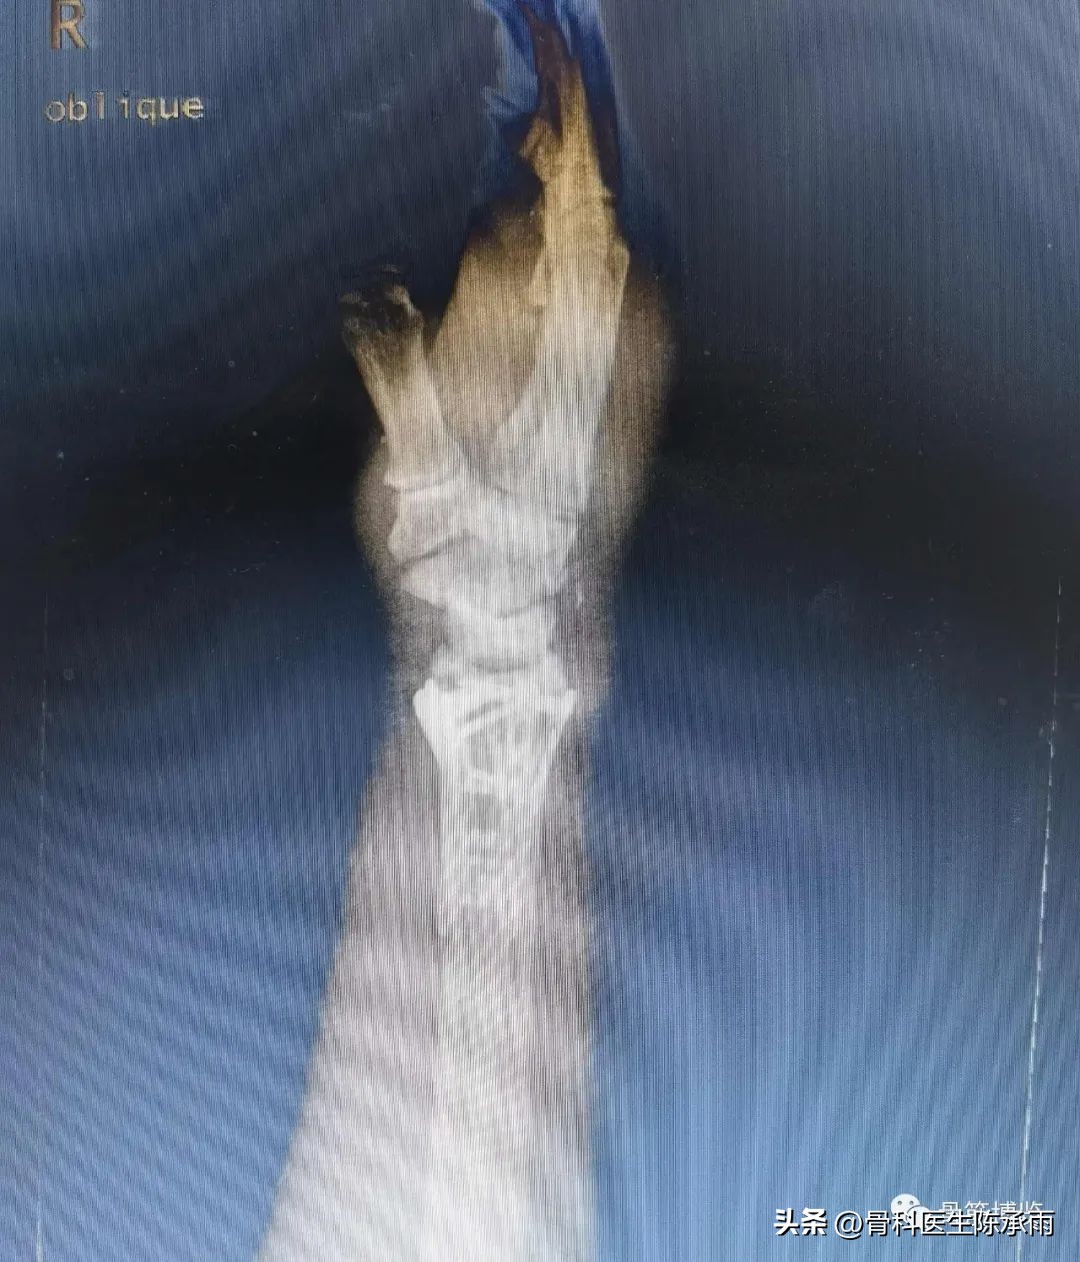

术前影像